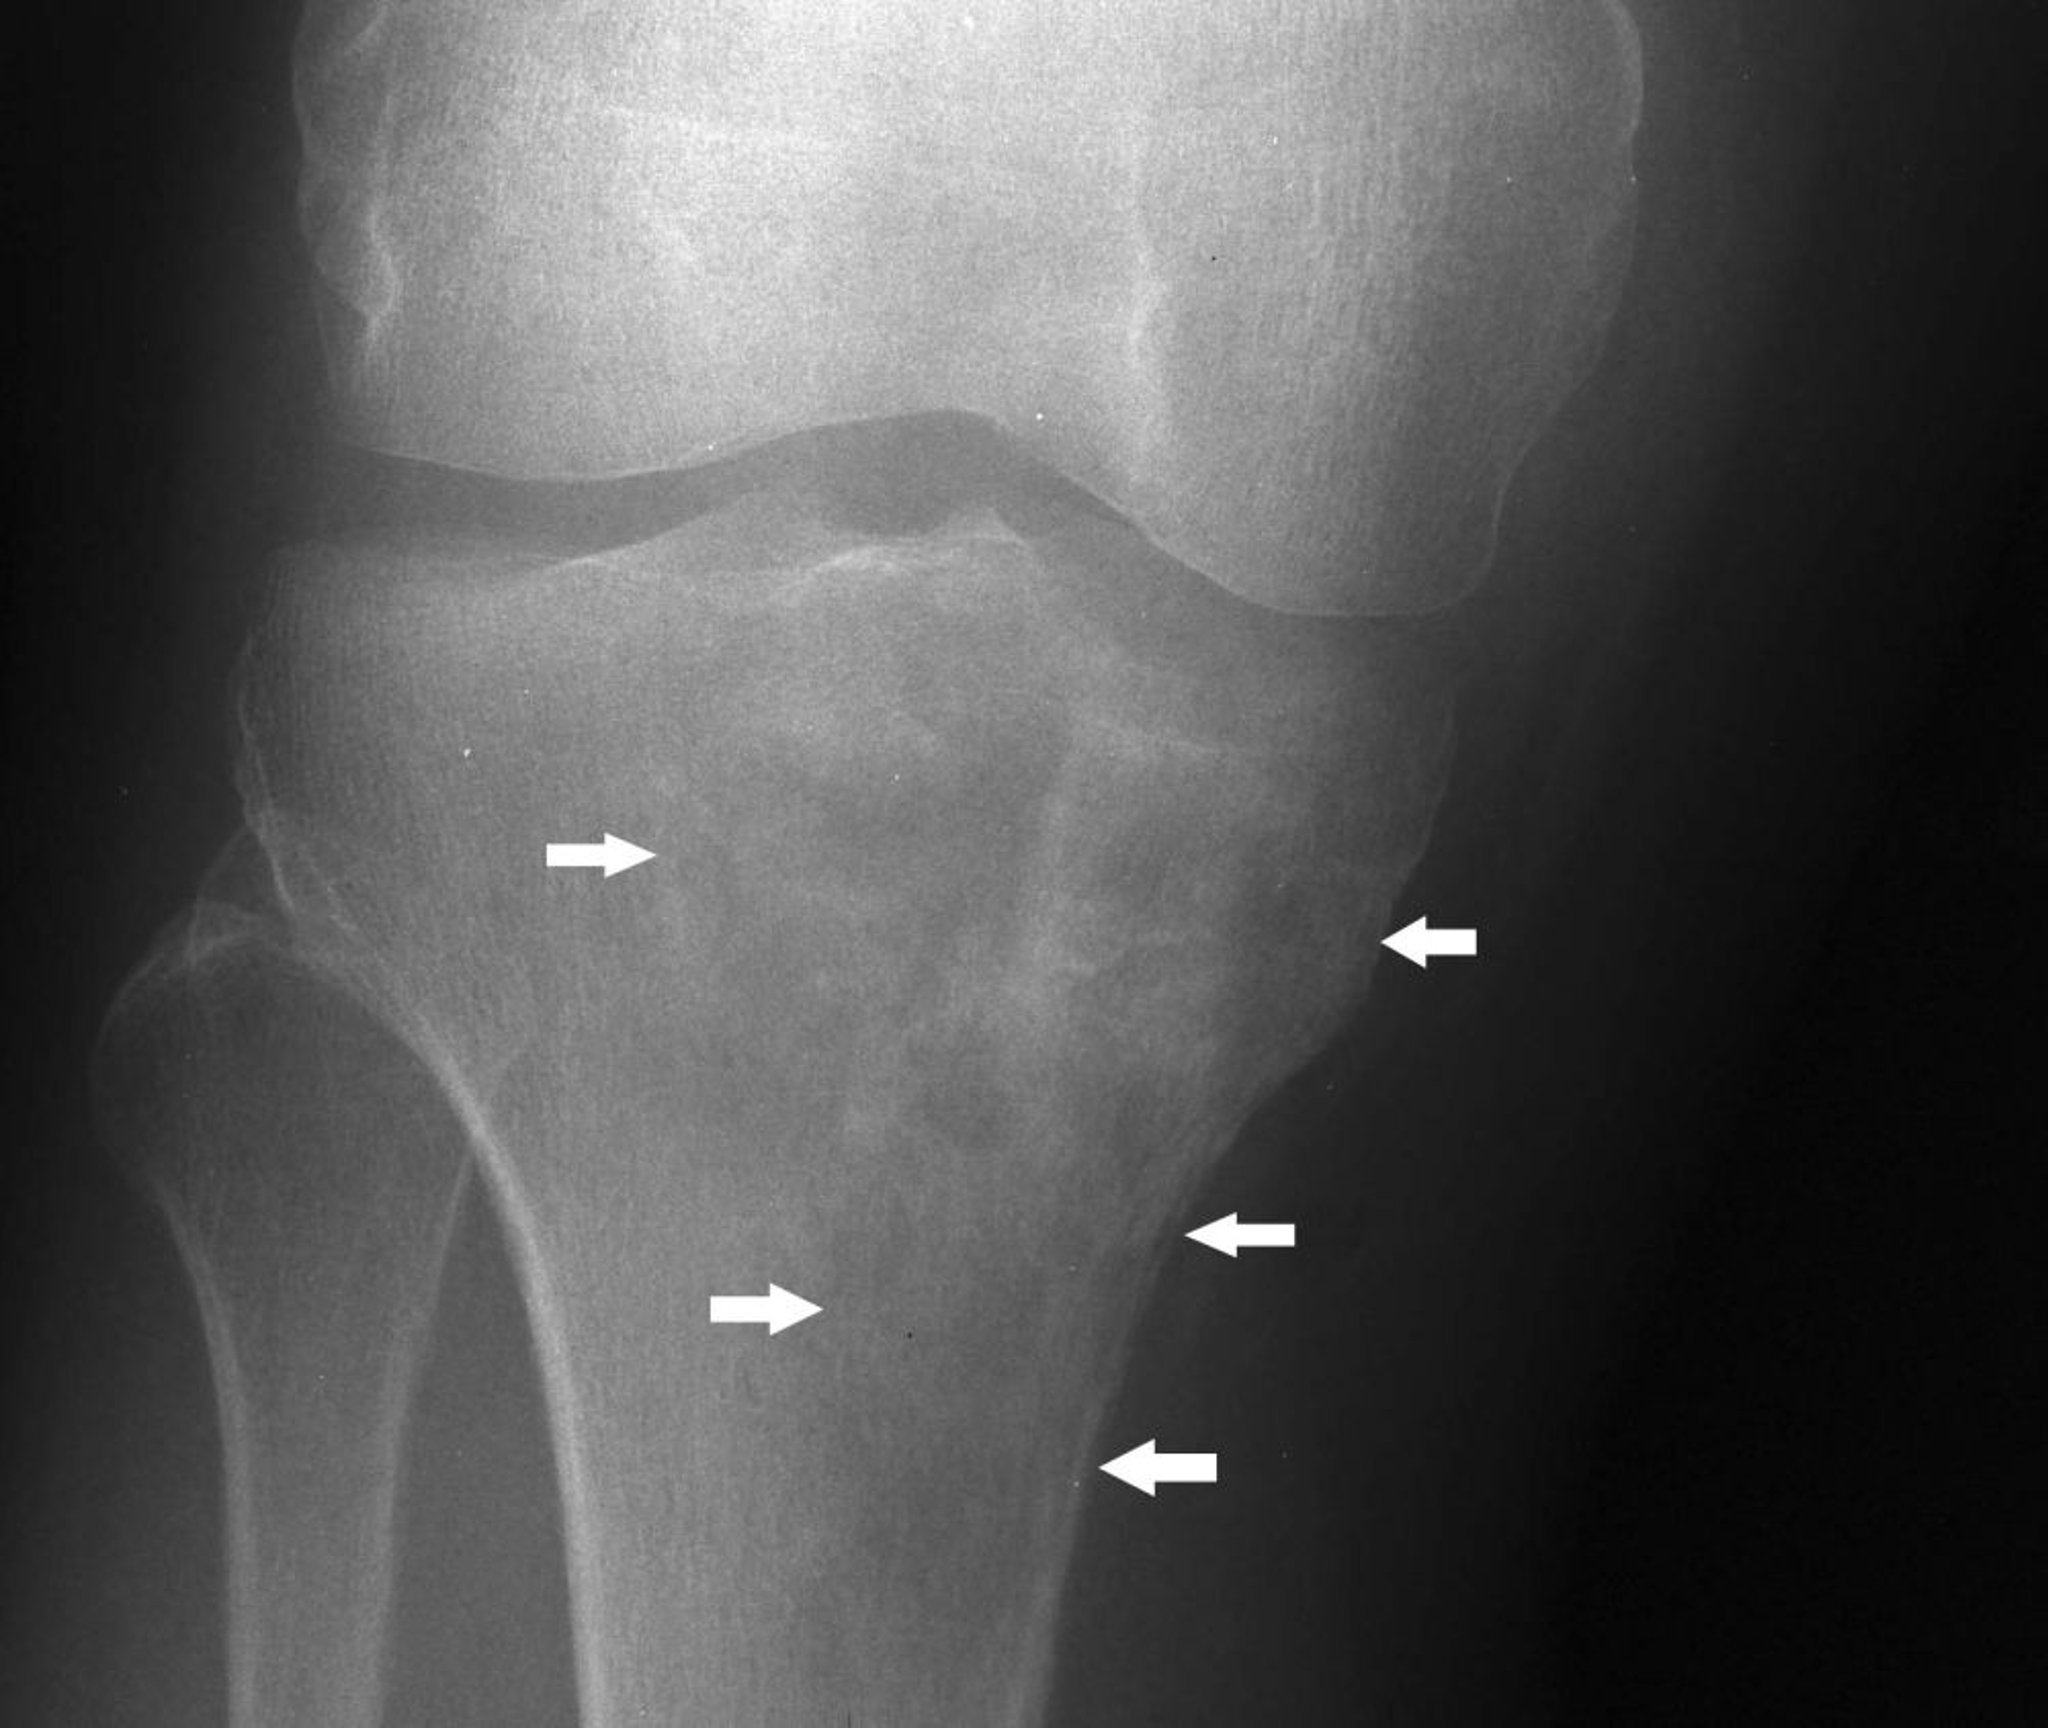

Lymphom des Knochens

Diese Röntgenaufnahme des Knies zeigt ein Lymphom in der proximalen Tibia mit einem gemischten lytischen und sklerotischen Erscheinungsbild unterhalb des medialen Tibiakondylus (Pfeile).

Image courtesy of Michael J. Joyce, MD, and Hakan Ilaslan, MD.